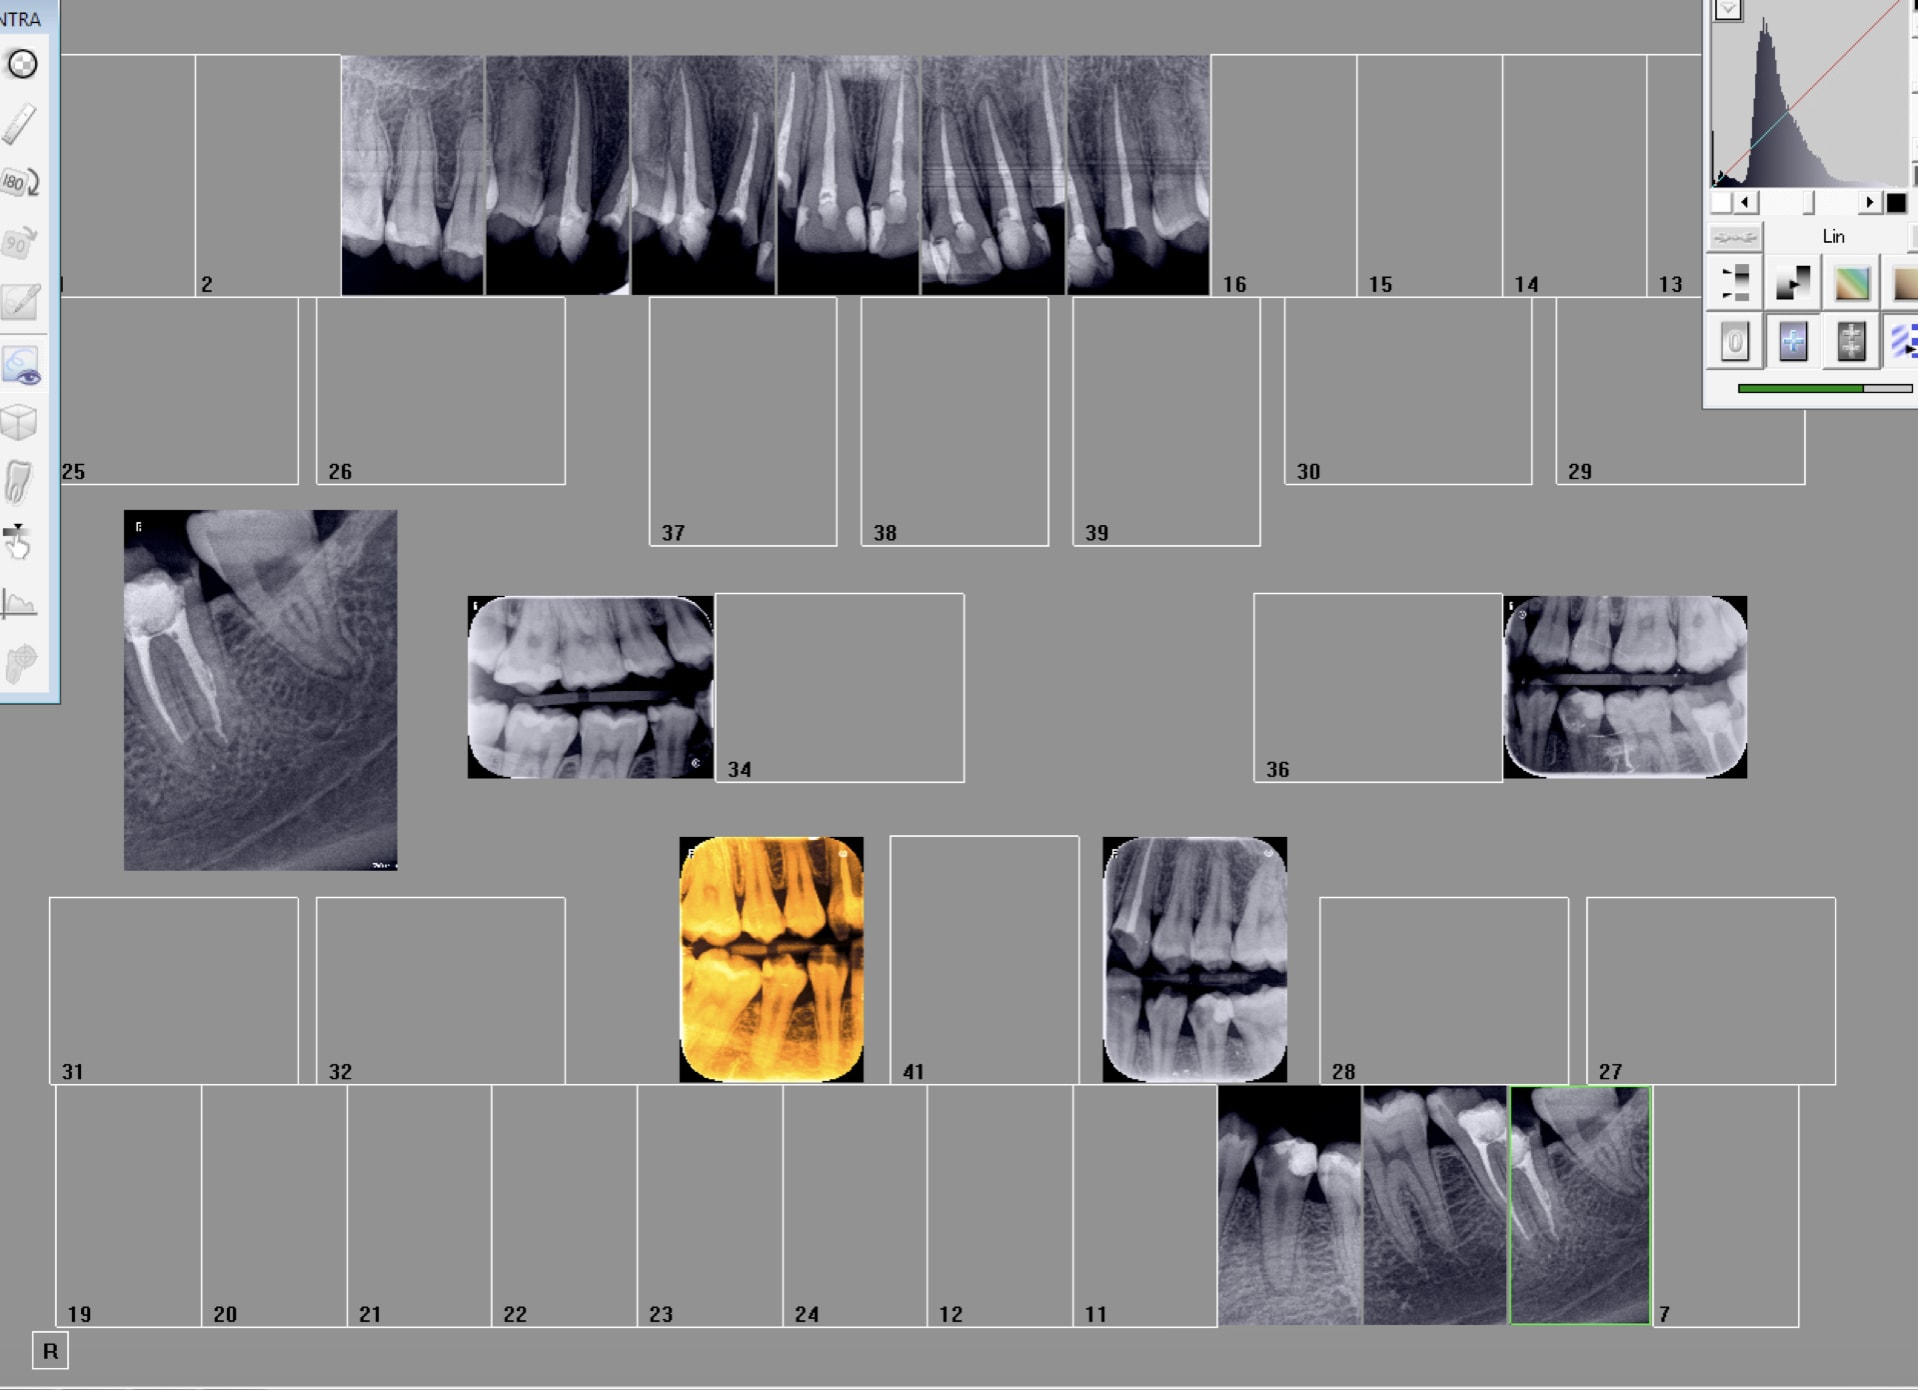

Là par exemple on aurait pu faire un status complet. Ceci dit c'est un peu chiant d'avoir toutes les dents parfaitement. Je préfère rétro coronaires + rétro alvéolaires ciblées. -)))